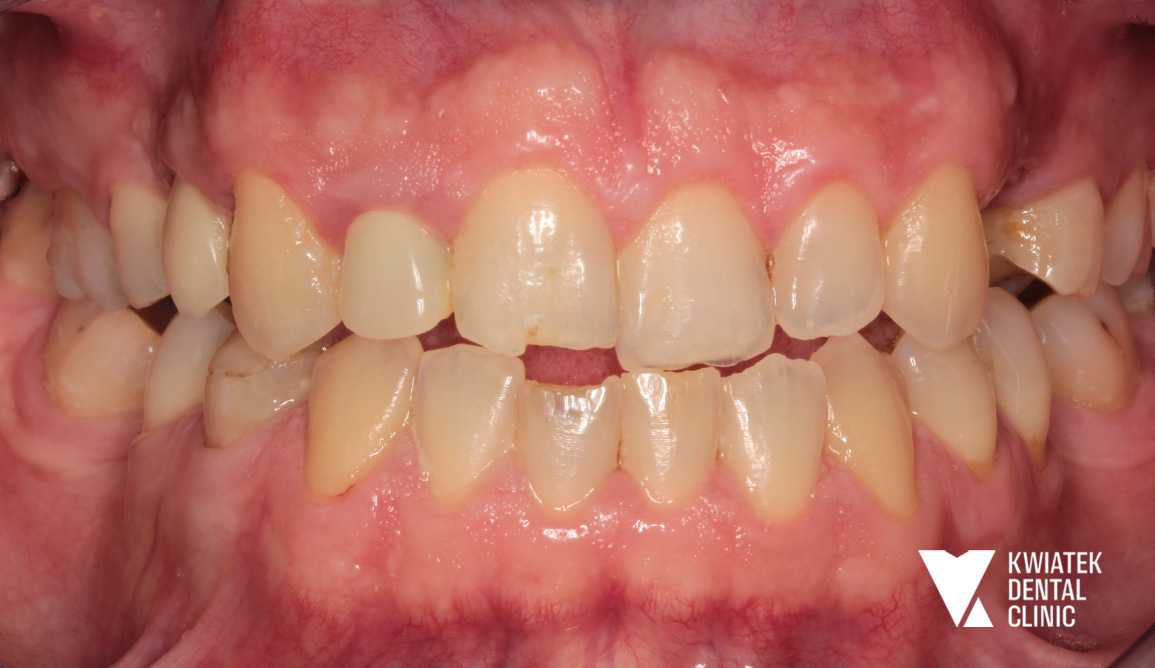

Efektem wieloletniej współpracy jest:

To metamorfoza, która nie wydarzyła się w jeden dzień. To historia uśmiechu tworzona wspólnie przez lata, w oparciu o potrzeby Pacjenta i indywidualnie dopasowane rozwiązania terapeutyczne. Nasi specjaliści wspólnie z Pacjentem tworzyli plany leczenia, a ich efekty dziś spotykają się w jednym miejscu podczas wizyt kontrolnych, które są naturalną kontynuacją tej relacji opartej na szacunku i wzajemnym zaufaniu.